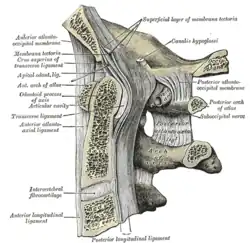

3D image Posterior atlantooccipital membrane and atlantoaxial ligament; the axis is visible at center.

Posterior atlantooccipital membrane and atlantoaxial ligament; the axis is visible at center. Median sagittal section through the occipital bone and first three cervical vertebra